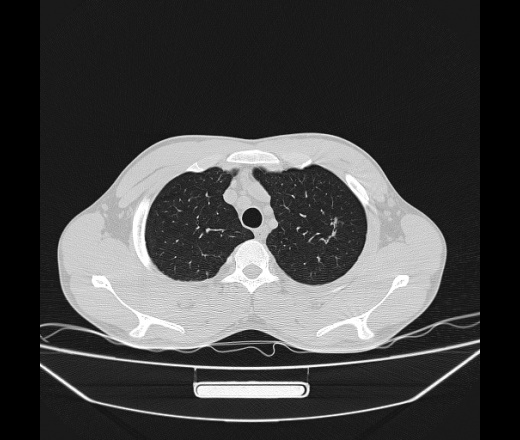

Молодой парень 18 лет, призывник, при прохождении ФЛС на верхушек левого легкого выявили очаги средней интснисвности с нечеткими контурами, тяжи. Сделали бок и томограммы 6-7-8. Везде описывают как очаговый твс. Вижу только перибронхиальный фиброз. Что за изменения в бронхах, указано нижи стрелками, тоже перибронхиальный?

Не стал бы говорить об очагах. Акцентировал бы не на фиброзе, а на тракционных бронхоэктазах. Не обязательно они результат tbc бронхов, но проверить не помешает.

Иван, пациент ведь уже "направлен с ОПТД", так?surprise Возвращайте его назад с заключением о возможном микобактериозе. Остаточные поствоспалительные ( посттуберкулёзные?) в дифряд.Очаговый твс с неясной активностью они уже себе "нарисовали", как я поняла.

+1 за микобактериоз.